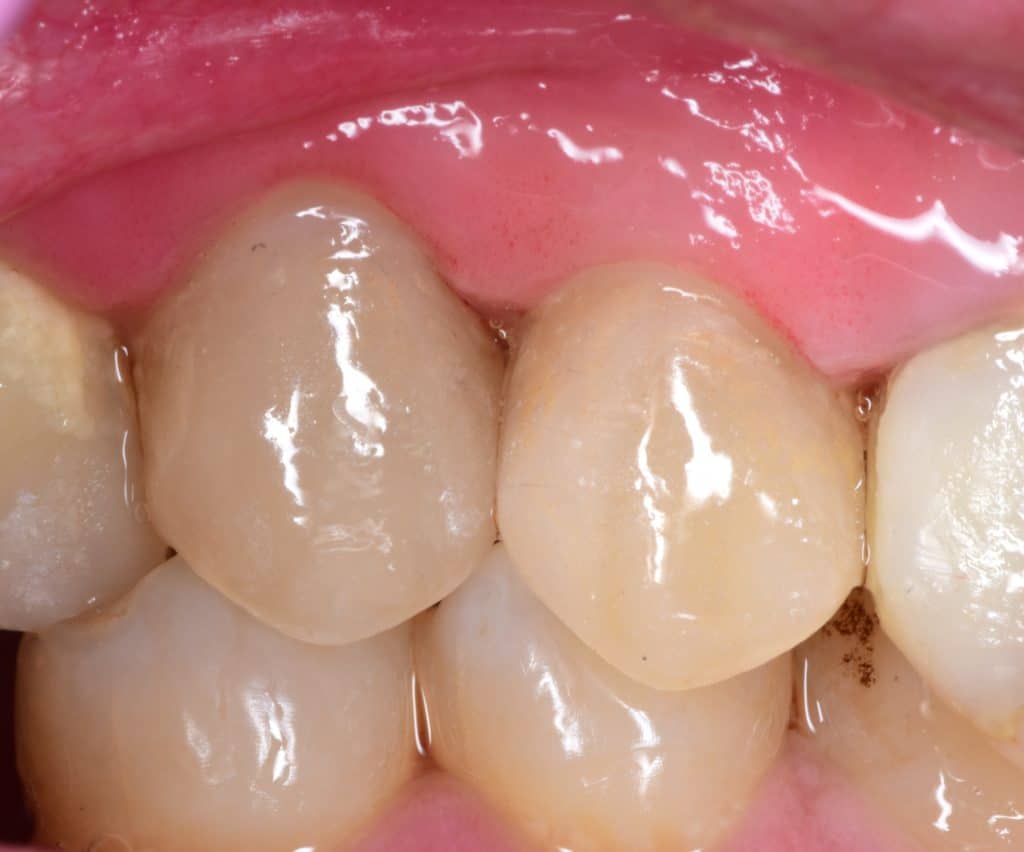

Immediate result, buccal view in occlusion

2 weeks later

2 weeks later, healing 💖